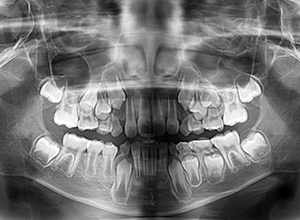

| X-Ray所見 | |

| セファロ所見 | 上下顎骨は調和のとれた位置関係を示していたが、頭蓋に対して両顎共に前方に位置していた。上下顎前歯は唇側傾斜していた。 |

| パノラマ所見 | 過剰歯抜歯後は特に問題ない。 |

| 既往歴として上顎正中過剰歯(2本)は抜去済み。その影響で上顎右側中切歯は捻転して萌出しており、下顎右側中切歯と早期接触が認められたため2x4(上顎のみブラケット装着)にて前歯部の改善を行った。現在は永久歯列完成まで経過観察を行い、希望があれば口元の突出感を改善するために本格矯正治療を行うことにしている。 | |